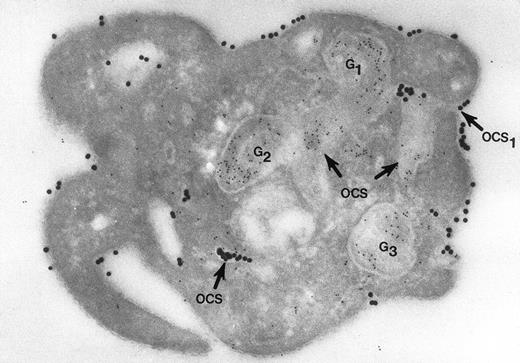

Cryosection of blood platelet from a washed cell suspension incubated with 18- to 20-nm colloidal gold particles coated with Fgn/Au for 5 minutes, then exposed to 1 U/mL of thrombin for 60 seconds. The Fgn/Au particles bind to the cell surface and penetrate into peripheral channels of the OCS. After fixation, freezing, and cryotomy, the frozen thin section was stained with a polyclonal antifibrinogen antibody and protein A bound to 5-nm gold particles. Immunogold beads detecting endogenous fibrinogen are concentrated in intact granules (G3) and in granules (G1, G2) in the process of discharging their contents into channels of the OCS. Some of the Fgn/Au particles entering from the outside are mixed with the immunogold beads in the same OCS channels (OCS) communicating with the exterior surface. Original magnification ×60,000. (Reprinted with permission.18)

Nor would Morgenstern have made the comment that fusion of membranes of secretory organelles with membranes of the OCS has never been shown. The reports from our laboratory that he cited, and others,18 answer this concern quite well. In one of the experiments, platelets in suspension were combined with 20-nm colloidal gold particles coated with fibrinogen (Fgn/Au), then exposed to thrombin for 1, 3, and 5 minutes without stirring.19 At these intervals the platelets were fixed, frozen, and frozen thin sections prepared. The sections were stained with a polyclonal antifibrinogen antibody and then staph protein A bound to 10-nm gold particles. Thrombin stimulated uptake of 20 nm Fgn/Au gold particles into OCS channels and their transfer to α granules in the process of discharge into the OCS (Fig 1). Protein A 10-nm gold particles demonstrated fibrinogen in nonlabilized α granules and those in the process of discharge into the OCS. The work showed that the OCS was truly a final common pathway; hence, the name of the article.19